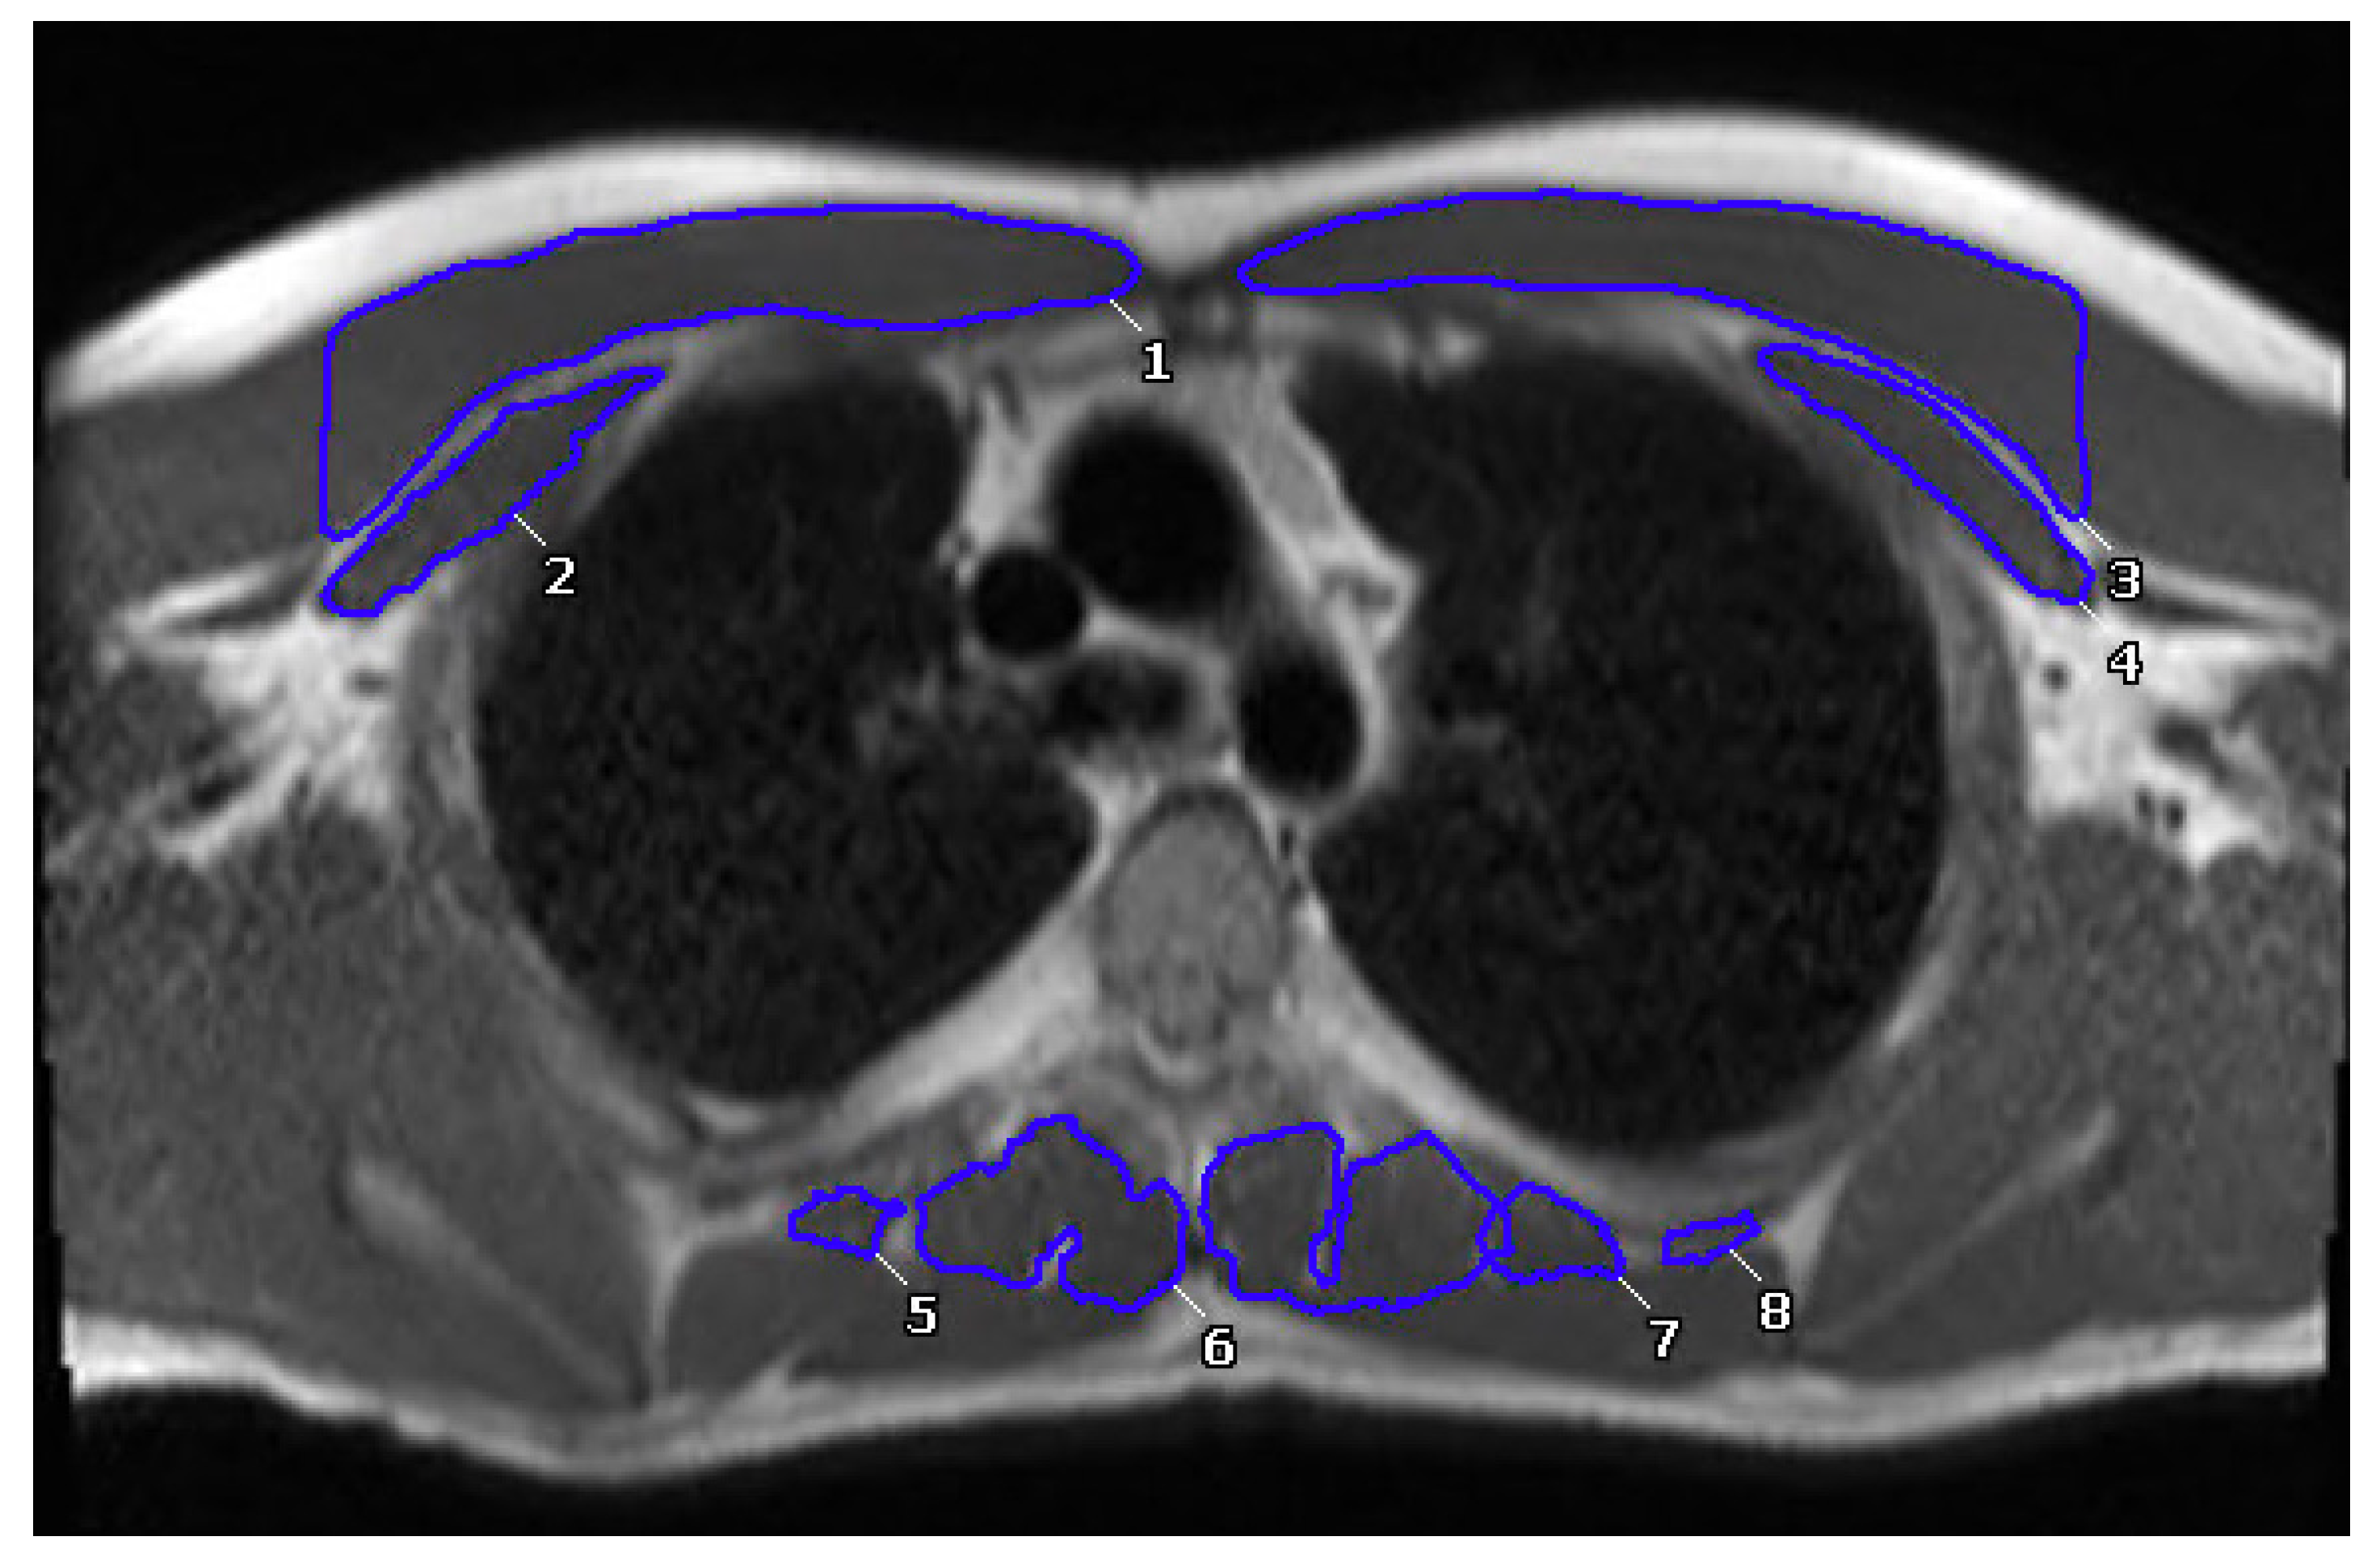

2.4. Muscle Measurements